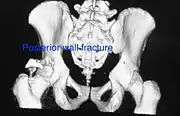

Posterior wall fracture as seen on 3-D CT scan

| Posterior wall | This is the most common variety of acetabular fracture. It typically occurs due to dashboard injury; when a person travelling in a vehicle involved in a head-on collision, the force applied over the flexed knee travels along the femur bone to the head of the femur, breaking the posterior wall of the acetabulum. The head of the femur is dislocated outside the joint. | T shape | When a transverse fracture also had a vertical fracture line, it is called a T shape fracture. Here the innominate bone is broken in such a way that all three parts of it, the ilium, the ischium and the pubis are separated from one another. This is a three part fracture. Though both columns are broken, the weight bearing dome is still attached to the main part of the ilium and hence it is not a true fracture of both columns.